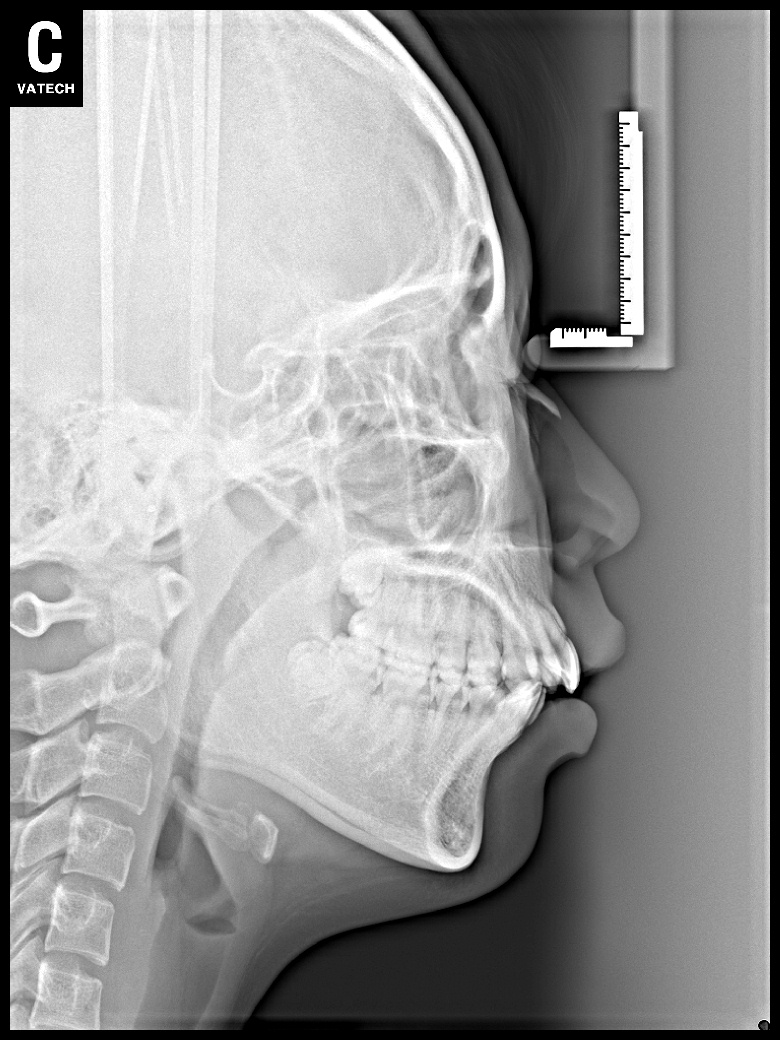

치료 전 사진입니다.